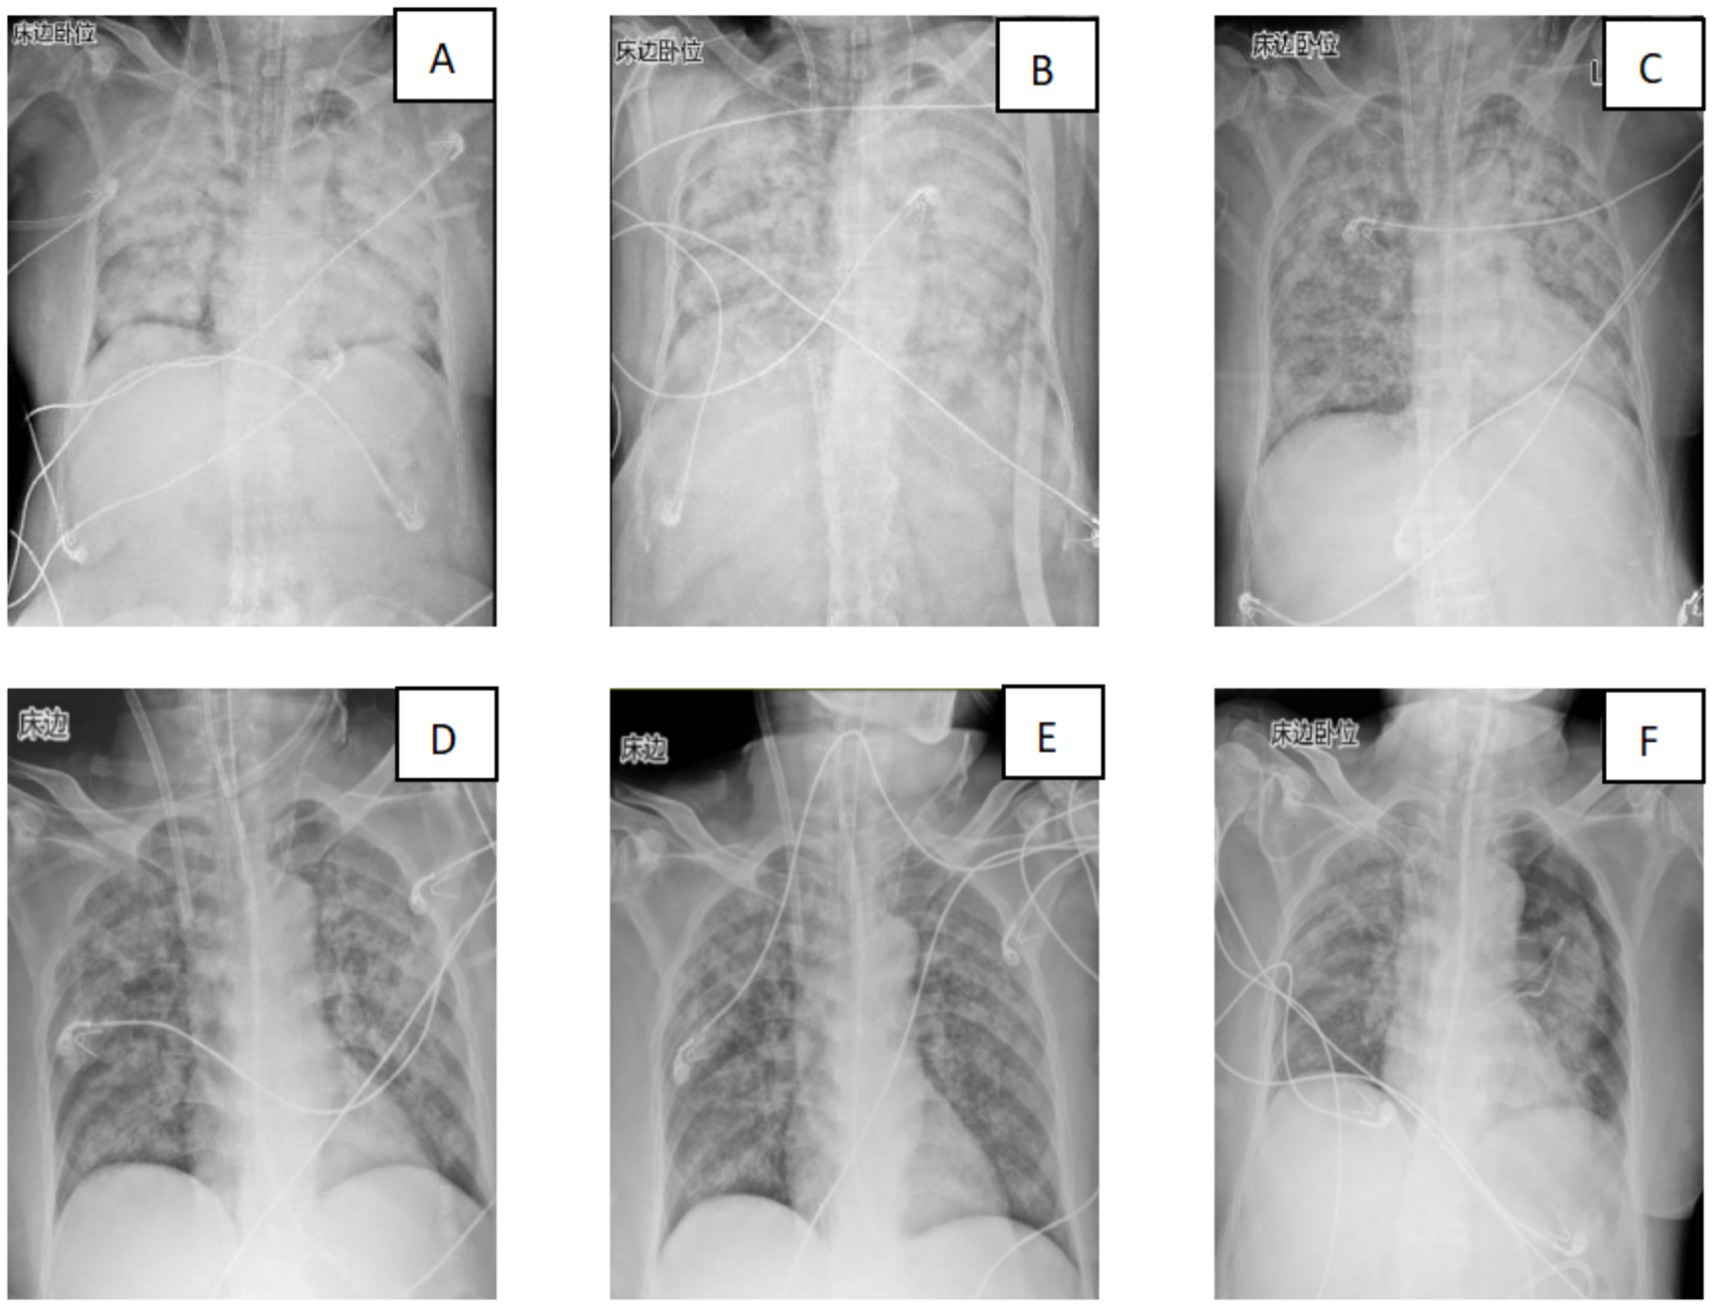

Over the subsequent 24 h, the patient’s condition deteriorated rapidly. Progressive dyspnea developed, and arterial blood gas analysis indicated severe hypoxemia (partial pressure of arterial oxygen/fraction of inspired oxygen ratio [PaO₂/FiO₂] = 107 mmHg) despite optimal mechanical ventilation settings. Chest radiography demonstrated diffuse bilateral infiltrates, consistent with acute respiratory distress syndrome (ARDS) (Figure 2). Bronchoscopy revealed massive endobronchial bleeding, indicative of severe pulmonary hemorrhage (Figure 3). Considering the patient’s rapidly worsening respiratory status and presence of multiorgan dysfunction, a diagnosis of severe leptospirosis with pulmonary hemorrhage was suspected. As this pathogen is not commonly encountered in our hospital, specific antigens for the microscopic agglutination test (MAT) were not available. However, microscopic examination of bronchoalveolar lavage fluid collected via bronchoscopy revealed Leptospira (as shown in Figure 4). After 48 h, polymerase chain reaction (PCR) results from the patient’s blood and alveolar lavage fluid samples confirmed the presence of Leptospira DNA and additional Mycobacterium chelonae and Aspergillus flavus. The diagnosis of leptospirosis with hemorrhagic lung manifestation was thus confirmed.

Figure 2

Six chest X-ray images labeled A to F. Each X-ray shows the lungs with varying degrees of opacity and clarity, indicating different levels of infiltration or fluid accumulation. Various medical tubes and lines are visible, highlighting patient treatment.

Figure 2. Changes in the patient’s lung imaging (A: 29th July; B: 30th July 30; C: 31st July; D: 2nd August; E: 3rd August; and F: 11th August).

Over the following days, the patient’s condition gradually improved. The volume of endobronchial bleeding decreased, and the oxygenation index continued to improve. On day 4 of ECMO support, the patient’s lung exudation had decreased compared to before, and oxygenation had begun to improve. On day 8, following a comprehensive assessment of respiratory function, oxygenation status, and overall clinical condition, the decision was made to wean the patient from ECMO. The weaning process was uneventful, and the ECMO circuit was successfully removed. The patient was then gradually weaned off mechanical ventilation over the next 3 days.

The patient was transferred to the general ward on day 15 after admission. Follow-up laboratory tests showed normal liver and kidney function, and the complete blood count had returned to normal. The patient was discharged on day 18 with a prescription for oral doxycycline for a total of 14 days. At the 2-week follow-up visit, the patient reported no residual symptoms, and chest radiography showed complete resolution of pulmonary infiltrates.